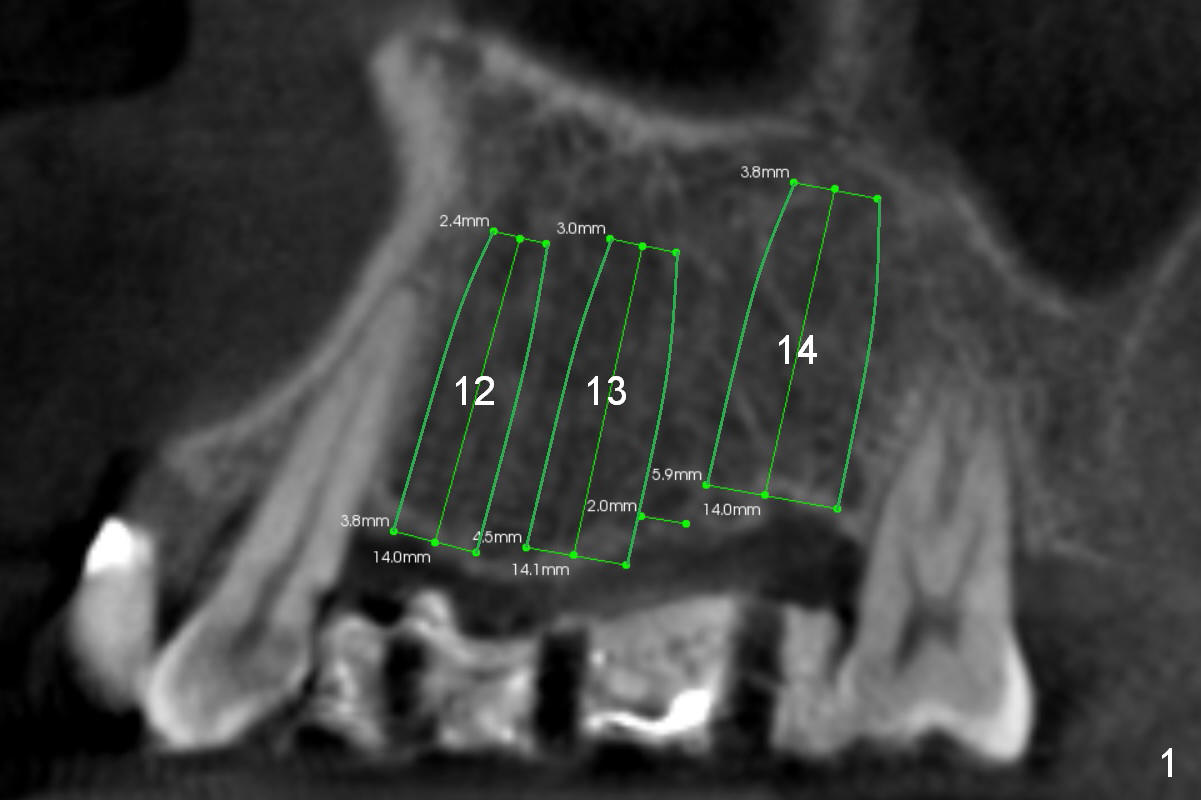

Three implants will be placed in the upper left posterior sextant (Fig.1-4). Without incision, place a surgical stent with trajectory tubes in place. Start osteotomy through the metal tubes (Fig.5,6) with a 2 mm pilot drill (SM) with drill extension if necessary. Palpate the buccal plate while drilling. Insert parallel pins for PA. According to the size of keratinized gingival band in the edentulous area, use either a 4 mm tissue punch or #15 scalpel for access. This way favors the trajectory over the diameter and length of the implants.